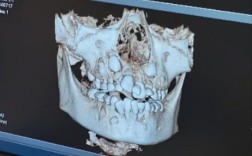

| CBCT(锥形束CT) | 口腔颌骨的三维立体影像,可任意层面重建(冠状位、矢状位、横断面) | 精确观察牙根位置、牙根间距、骨量是否充足、埋伏牙的具体位置与方向、邻牙牙根是否受压,是复杂病例(如正畸-正颌联合治疗)的必备工具。 |